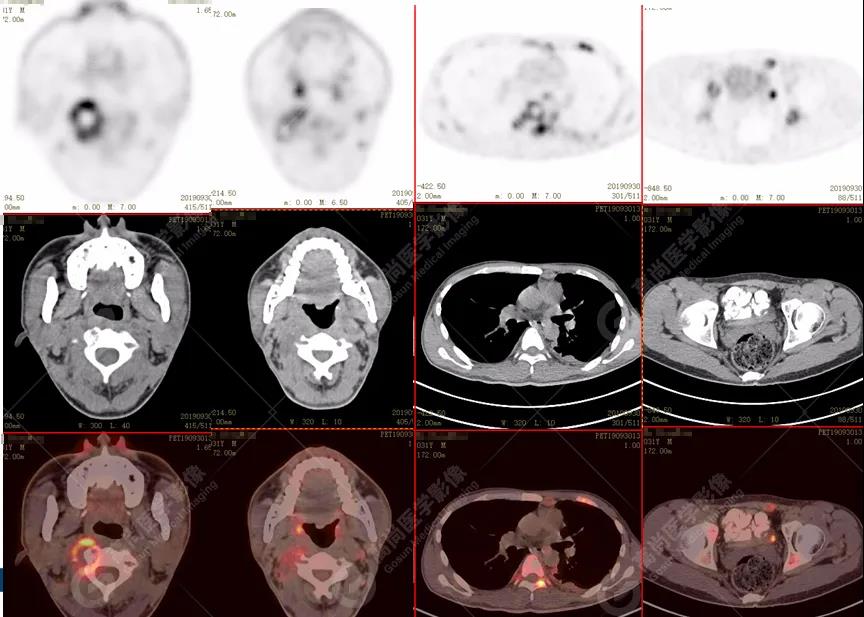

脊柱多發(fā)椎體及附件骨質(zhì)破壞,代謝不均性增高

全身多發(fā)高代謝腫大淋巴結(jié),中央代謝缺損

左肺上葉尖后段及下葉背段多發(fā)簇狀斑點(diǎn)狀高代謝灶

左側(cè)胸膜結(jié)節(jié)樣增厚,代謝不同程度增高

雙肺、左側(cè)胸膜多發(fā)結(jié)節(jié)影,全身多處骨質(zhì)破壞,全身多發(fā)淋巴結(jié)腫大,代謝攝取不均勻性增高。

2.全身多系統(tǒng)、多形態(tài)、多發(fā)病灶(肺部、胸膜、淋巴結(jié)、骨),18F-FDG攝取不均性增高;

特征:肺部病灶簇狀分布,上葉尖段及下葉背段為著;腫大淋巴結(jié)分布不對(duì)稱,無融合、中央有壞死改變,與淋巴瘤、轉(zhuǎn)移瘤等有一定的鑒別診斷意義;

診斷意見:綜合考慮感染性病變(結(jié)核),建議相關(guān)實(shí)驗(yàn)室檢查。